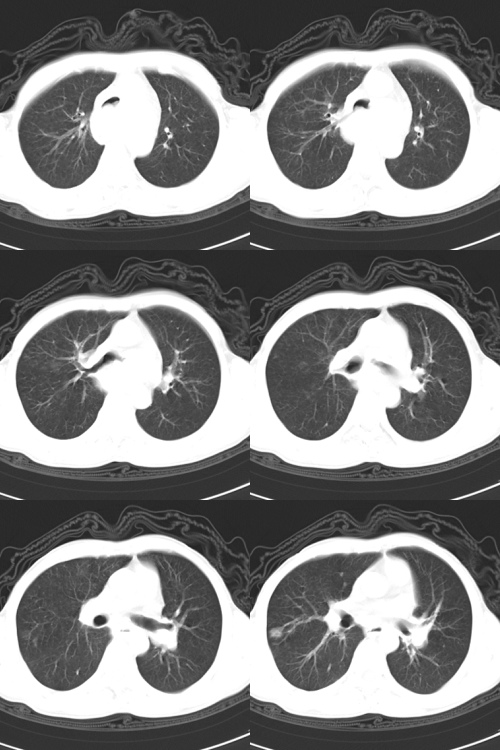

以下是引用zsl6918在2009-2-7 7:38:00的发言:[br]恶性度极高的肺癌,肺门及纵隔淋巴结转移。

以下是引用余辉在2009-2-7 8:29:00的发言:[br]考虑左下肺周围型肺癌伴肺门、纵隔淋巴转移及右肺转移